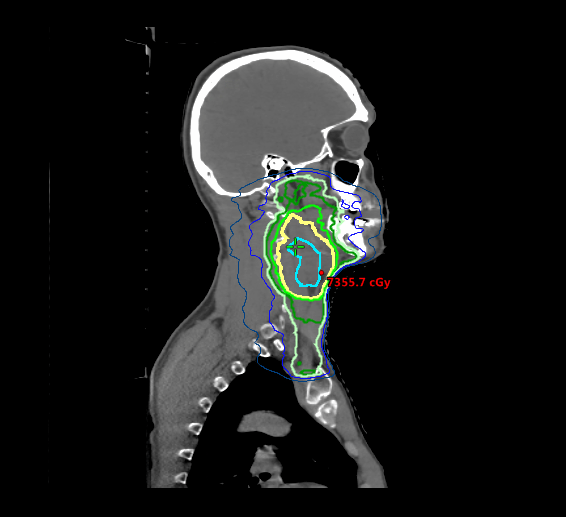

Cancers of the head and neck are among the most complex and challenging to treat, so Isaac’s care team, which included Kathryn Bollin, MD, medical oncologist at Scripps Clinic and Scripps Cancer Center, and Shane Mesko, MD, a radiation oncologist at Scripps Clinic and Scripps Cancer Center, quickly sprang into action.

An ultrasound revealed a lymph node measuring just under 6 centimeters, but the location of the primary tumor was initially unknown — a common diagnostic challenge in some types of head and neck cancers, says Dr. Mesko. A biopsy uncovered a small tumor in Isaac’s tonsil.

His physicians developed a treatment plan that included six-and-a-half weeks of near-daily radiation — 33 rounds in all — and weekly chemotherapy.